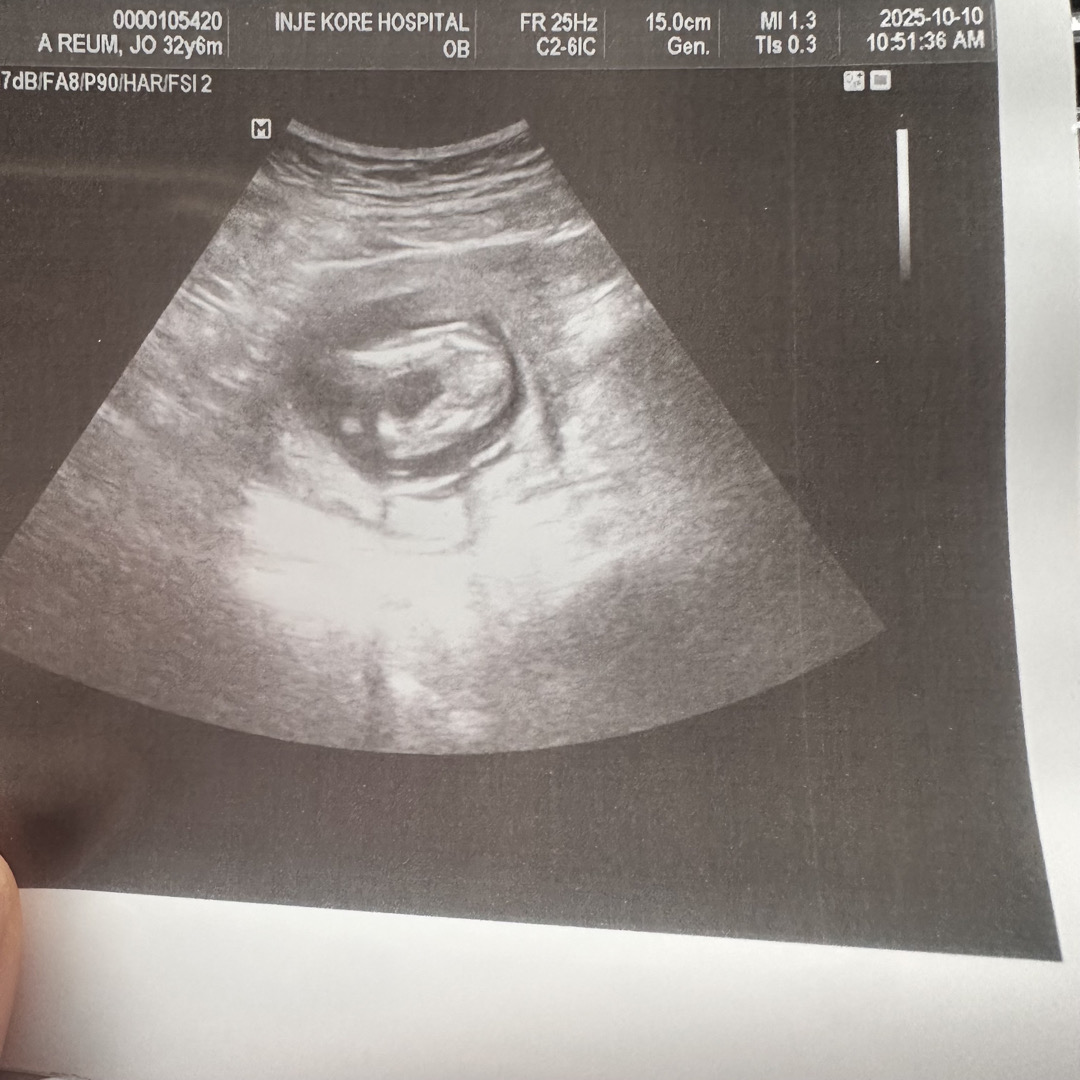

딸딸만 셋째성별 궁금해요15주3일

아무것도 없는거겟죠..?